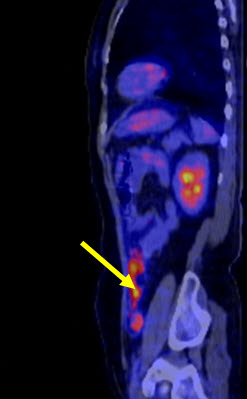

Hình 2. Bệnh nhân Lê Th. H., nữ, 58 tuổi, chẩn đoán: ung thư buồng trứng trái đã phẫu thuật và điều trị hóa chất năm 2011. Sau 8 tháng bệnh nhân kiểm tra thấy nồng độ chỉ điểm khối u CA 125 tăng cao (225ng/ml). Bệnh nhân được chỉ định chụp PET/CT kiểm tra. Trên hình PET/CT thấy tổn thương tái phát di căn màng bụng, trên hình CT không phát hiện được.